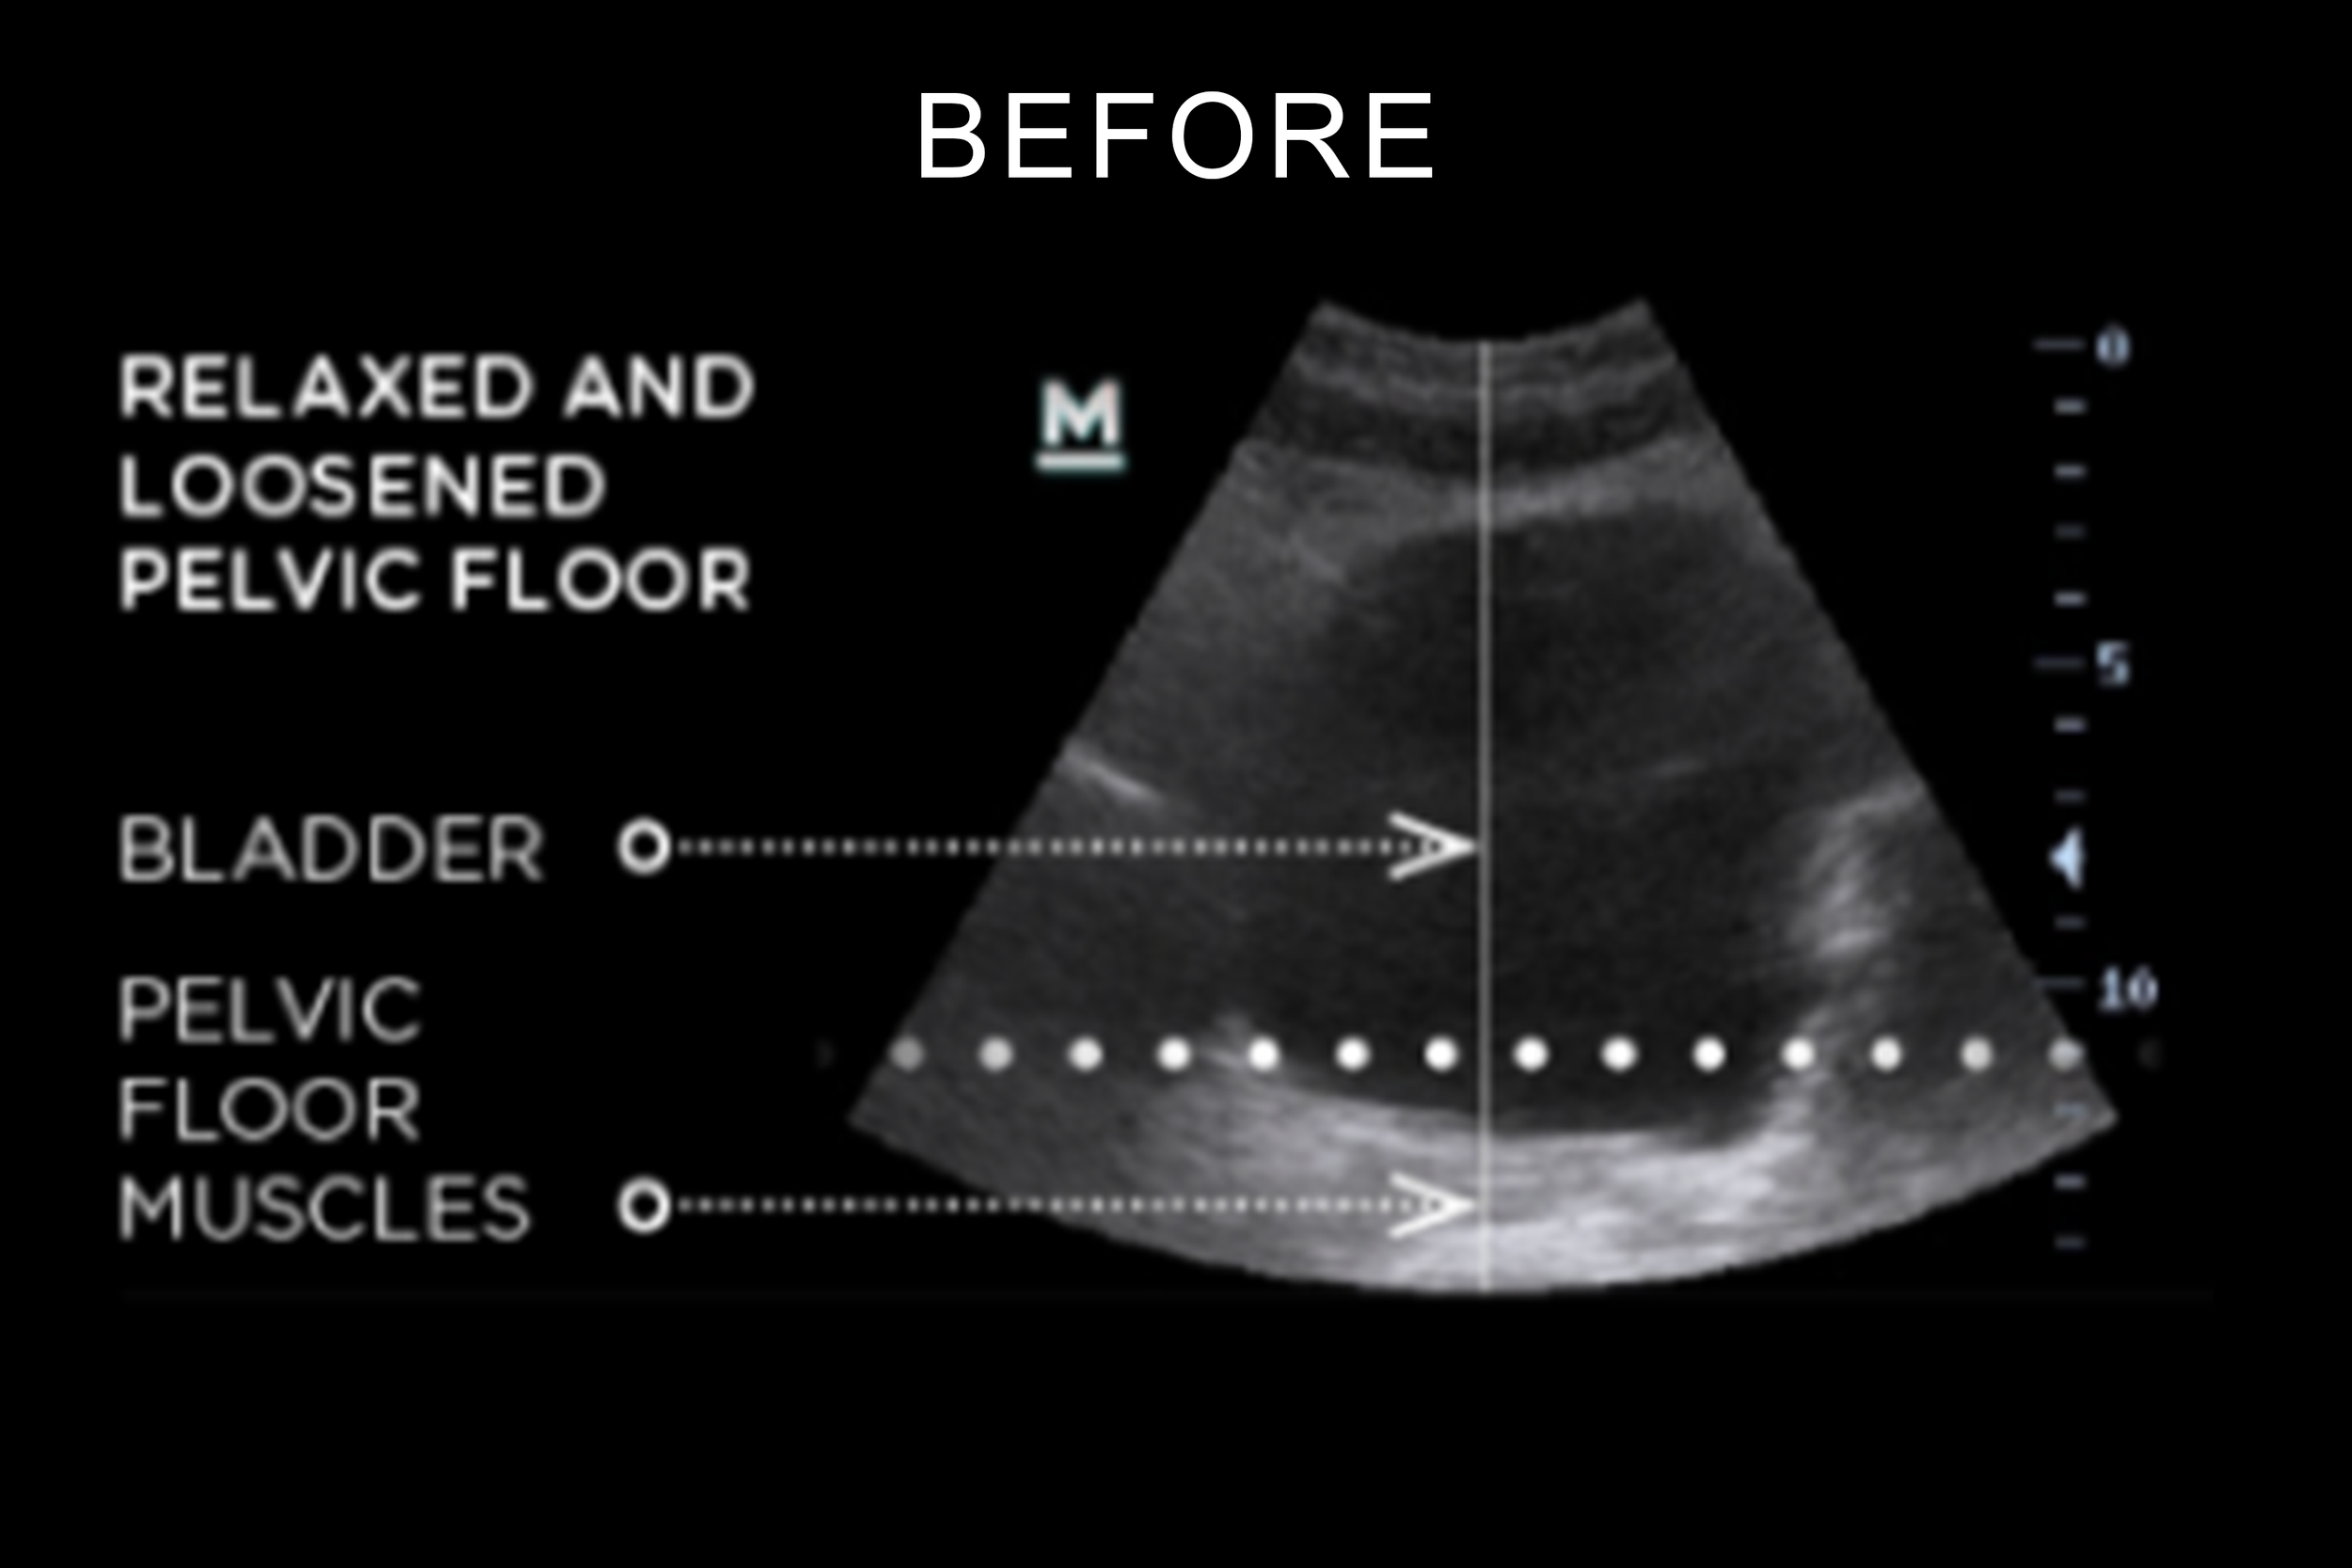

BEFORE / AFTER Photos

BTL EMSELLA is the HIFEM® procedure, that utilizes electromagnetic energy, at a high frequency, to cause pelvic floor muscle stimulation completely non-invasively. Similar to the contractions you perform when doing a Kegel exercise. What makes this treatment effective is the in-depth penetration and stimulation of the entire pelvic floor area. A single session brings you thousands of intense contractions that you would not be able to do on your own. These contractions are very helpful when it comes to muscle strengthening and re-education.

Q. What is the important of the pelvic floor muscles? A. The pelvic floor is a small but vital group of muscles that support your core and pelvic organs, playing a key role in stability and everyday function. Strong pelvic floor muscles help with daily activities like standing, walking, climbing, lifting and getting in & out of bed. When weakened, they can affect balance, bladder control, and overall comfort and confidence.

A. Urinary incontinence is defined as the involuntary leakage of urine. This might be a result of weak pelvic floor muscles since pelvic floor muscles play an important role in supporting pelvic organs and controlling continence.